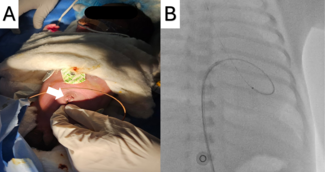

An 84-year-old man with a history of dyslipidemia and hypertension underwent invasive coronary angiography via his right radial artery because of acute coronary syndrome. After the procedure, a palpable pulse was noted in his right forearm,...